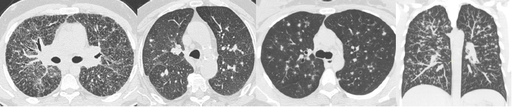

Micronodules

COCHE E. - 2021 - UCL

Cardio-thoracique DES SPECIALITE